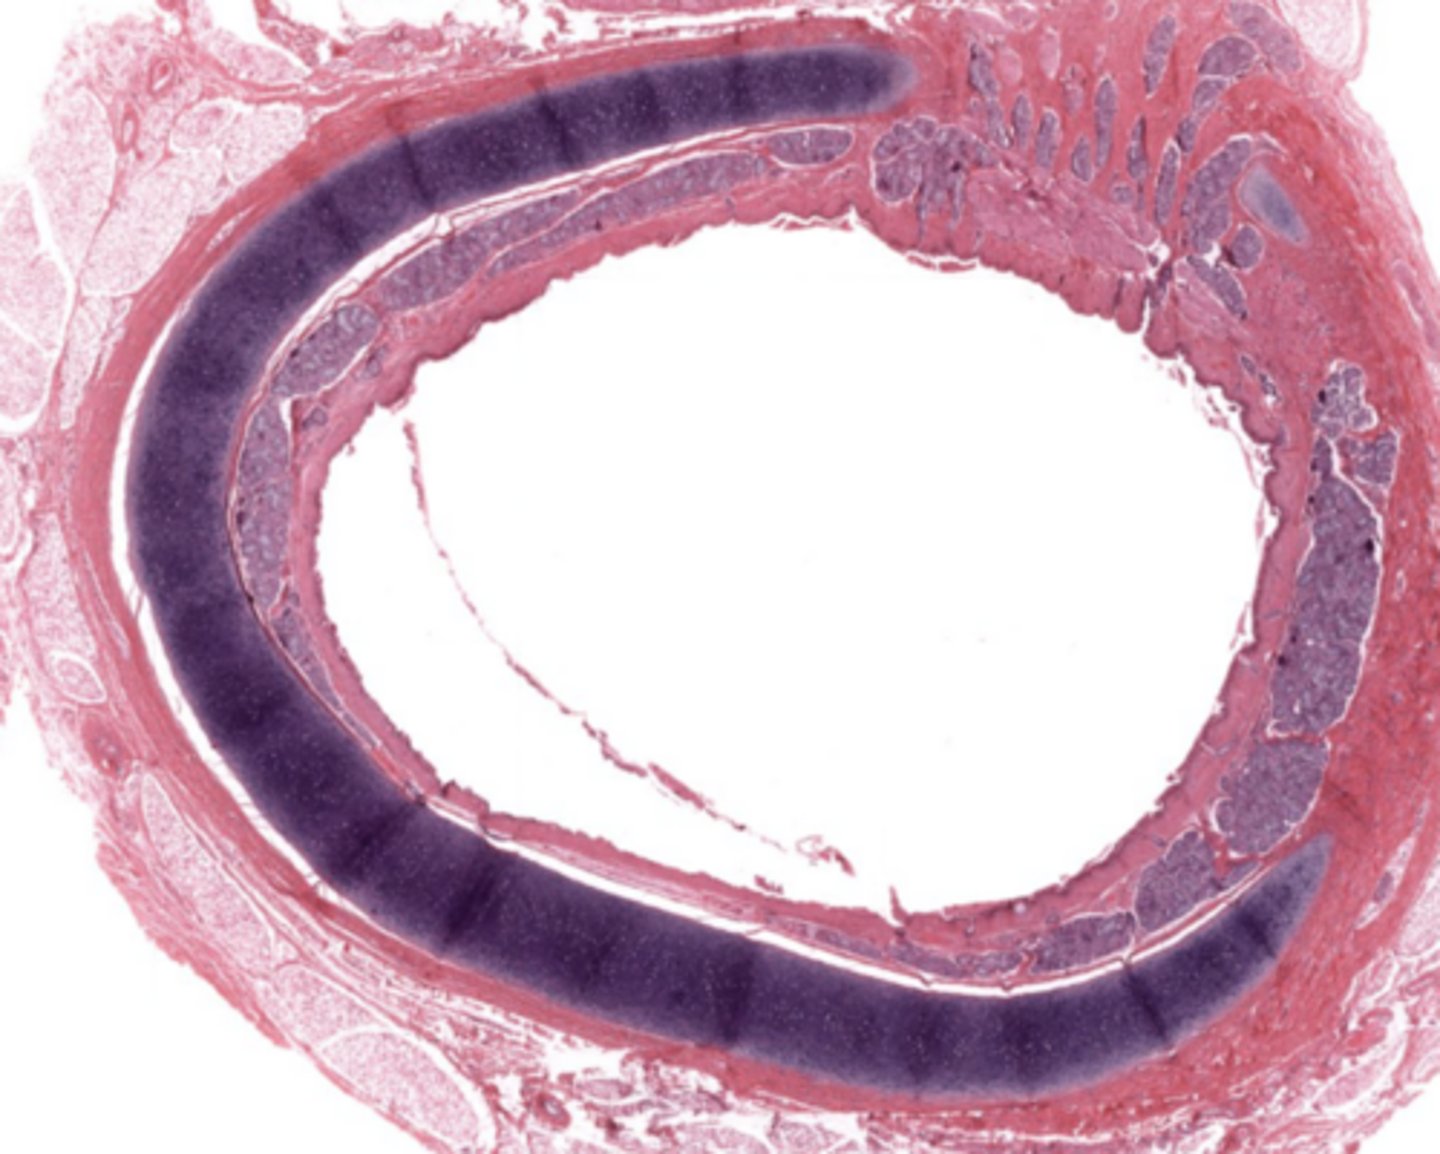

Larynx (voice box)

Identify the entire structure

From what embryologic structure is the trachea derived?

Primordial foregut, its a 10 cm flexible tube which extends from the larynx to the bronchioles

What layers make up the trachea?

What type of cartilage supports the trachea?

Hyaline cartilage (16-20 C shaped rings)

Why are the cartilage rings open posteriorly?

To allow flexibility next to the esophagus.

What completes the posterior gap of the cartilage ring?

Fibroelastic membrane with trachealis muscle.